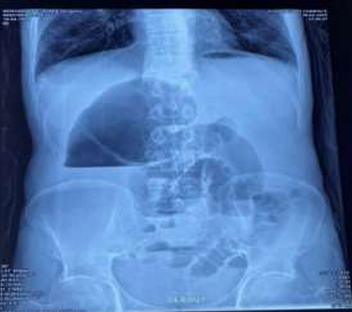

Radiographie de l’abdomen (ASP) : Position debout. Niveau hydro-aérique dans le cæcum gonflé. Anses iléales remplies de gaz latéralement au cæcum (fig 1).

Figure 1 : Niveau hydro-aérique (NHA) volumineux reflétant la distension du cæcum.

Le diagnostic repose rarement uniquement sur les signes cliniques, et la radiographie abdominale (ASP) joue un rôle essentiel. Le côlon dilaté présente un niveau hydro-aérique unique qui peut se trouver n’importe où dans l’abdomen, selon sa position initiale, le degré de distension gazeuse, le site, ainsi que le degré et la durée de la torsion. Il est typique d’observer des anses de l’intestin grêle distal sur le côté droit du côlon dilaté, tandis que le côlon distal contient peu de gaz.